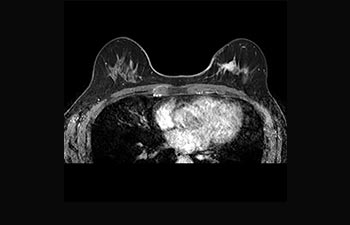

Sehen Sie selbst, was die ersten Nutzer von Ingenia Prodiva 1.5T über ihre Erfahrungen mit dem System und dessen Auswirkung auf ihre radiologische Praxis berichten.

Mehr Diagnosesicherheit in der Neuroonkologie